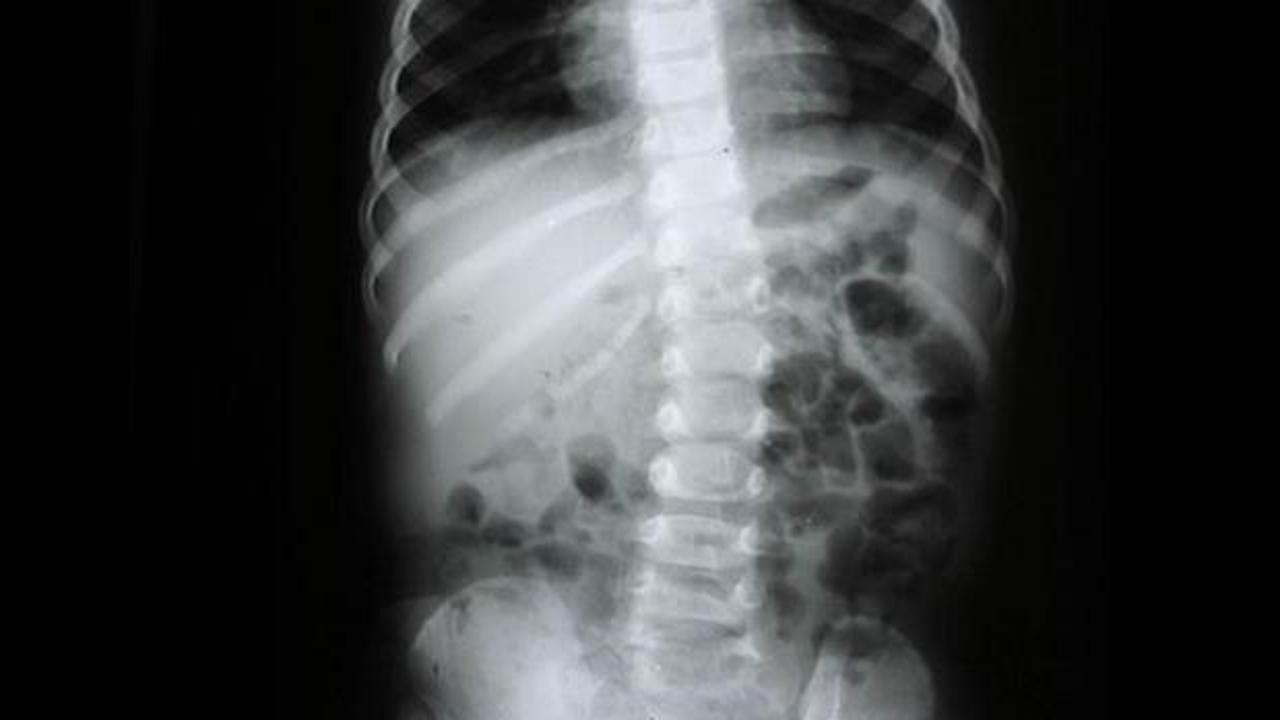

Omurgayı doğru desteklemeyen bir yatak, yıllarca süren kronik ağrıların, kas spazmlarının ve fıtığın habercisi olabiliyor.

OMURGA DOĞRU DESTEKLENMEZSE AĞRI KAÇINILMAZ

Kas ve iskelet sistemi sağlığında uyku pozisyonunun büyük önem taşıdığını belirten Doç. Dr. Hamza Sucuoğlu, “Günün yaklaşık 8 saati yatakta geçiyor. Bu süreç vücut için kritik bir önem sarf ediyor. Omurganın doğal eğriliklerinin korunması gerekiyor. Bu yüzden yatak ve yastık, vücudun anatomik yapısına uygun olmalı. Omurganın fizyolojik eğrileri korunmazsa kas spazmları, eklem problemleri ve kronik ağrılar ortaya çıkabilir. Özellikle yan yatış daha sağlıklı bir seçenek. Sırtüstü yatışta da omurgayı destekleyen ürünlerin tercih edilmesi gerekir.” dedi.